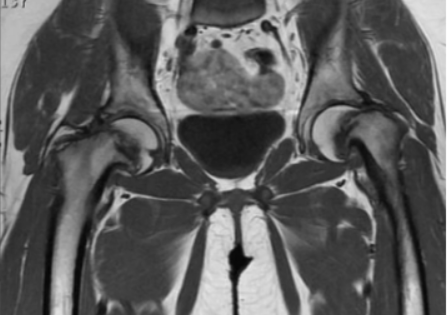

На снимке показан пример ишиофеморального импинджмента в хронической форме. Пациент - женщина в возрасте 60 лет. Жалобы - постоянные болевые ощущения в тазобедренных суставах, наиболее проявляющиеся в правом.

Гипертрофия седалищных бугристостей, ведущая к значительному сужению ишиофеморальных пространств; наблюдается деформация, отеки, несущественные скопления жидкости в квадратных бедренных мышцах (максимально заметные справа), неравномерная атрофические изменения с характерной жировой инфильтрацией.